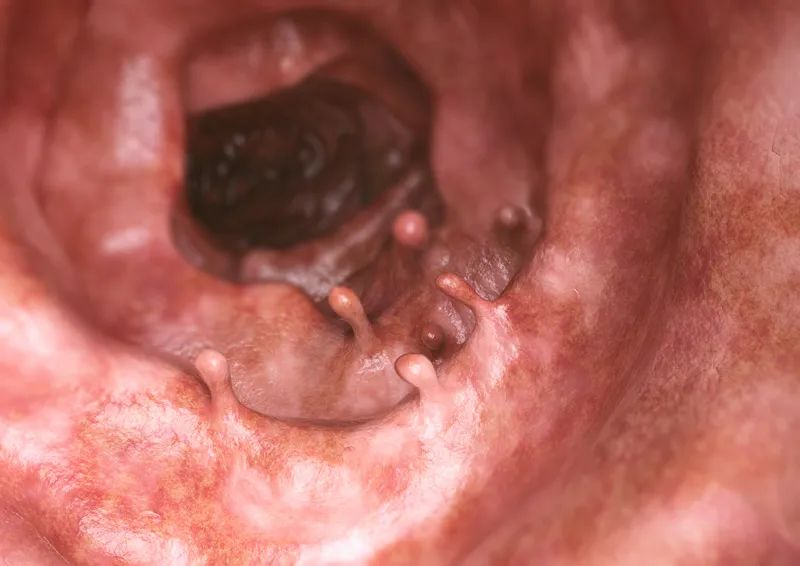

请注意!这6种常见病,有可能是“癌前病变”,千万别大意!

癌症,当然不是一下子就出现的,而是有一个缓慢进展的过程,这个过程有可能是几年,甚至是几十年。

如果能在癌症侵袭之前及早发现、及早治疗,毫无疑问是防治癌症蕞有效的手段。